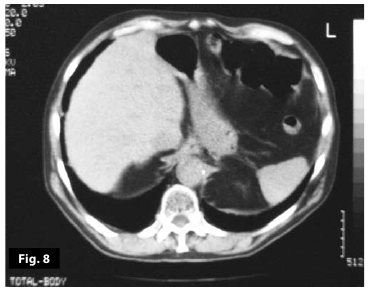

Figure7

Figure8

Figure7-8